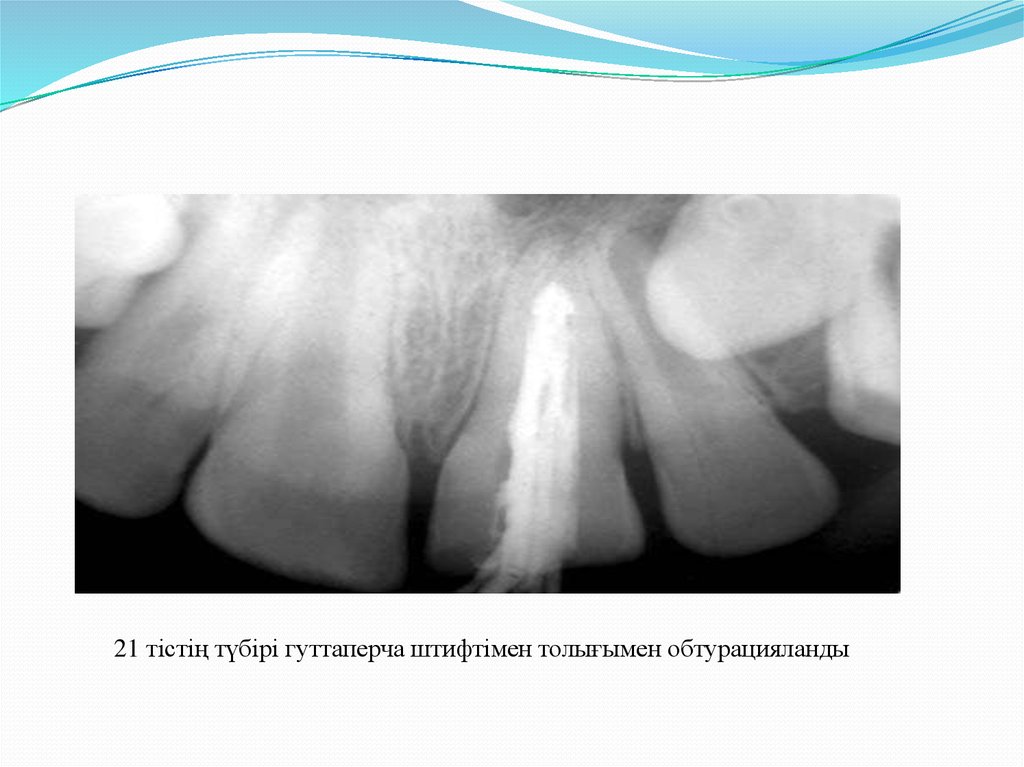

сутотығы пастасы ауыстырылды. 6 айдан кейін эндодонтиялық аспапты каналға

енгізген кезде «оң тоқтау» симптомы байқалды, рентгенограммада қатты апикальді

барьердің қалыптасуының басталуы анықталды. Апексификация ем жүргізілгенне 15

айдан кейін аяқталды. Клиникалық және рентгенологиялық дәлелденді. 21 тістің түбірі

гуттаперча штифтімен толығымен обтурацияланды.

21 тістің түбірі гуттаперча штифтімен толығымен обтурацияланды